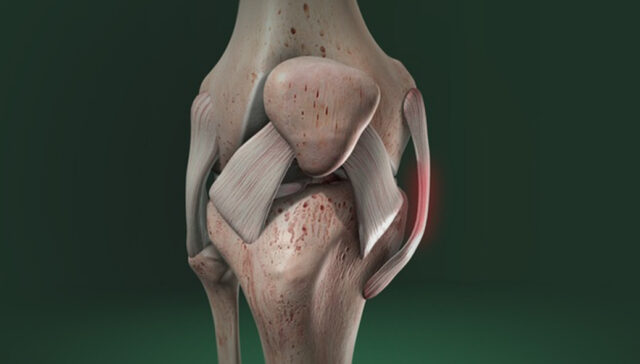

O Ligamento Cruzado Anterior é um dos ligamentos centrais do joelho que unem o fêmur (osso da coxa) à tíbia (osso da perna). Ele tem a função de impedir a anteriorização da tíbia em relação ao fêmur e tem uma importância fundamental na estabilidade rotatória do joelho. O principal problema relacionado à ruptura do LCA é a falta de segurança no joelho, com a sensação de que ele irá se deslocar.

A combinação mais comum de lesões multiligamentares no joelho envolve o rompimento do Ligamento Cruzado Anterior (LCA) e do Ligamento Colateral Medial (LCM). Quando